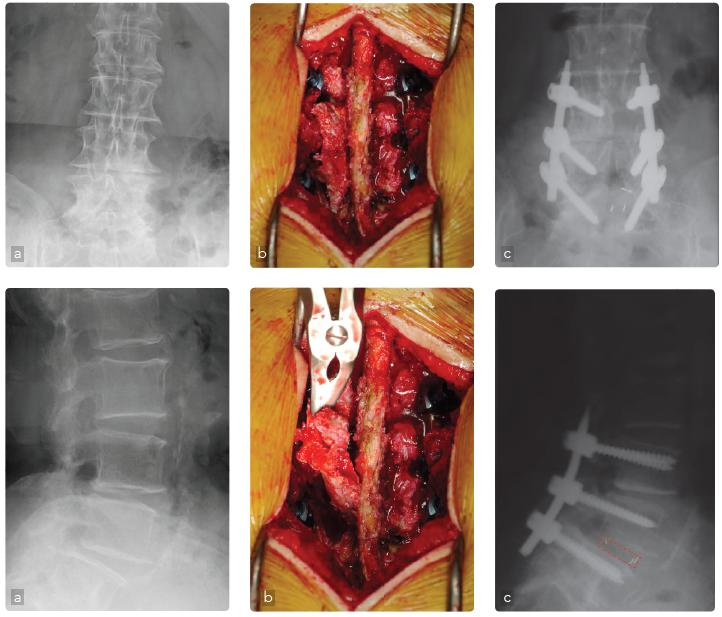

Caso 2: Stenoinstabilità lombare

Maschio, 64 anni, stenosi lombare. Da circa 10 anni lamenta lombalgia ingravescente con episodi di cruralgia e sciatalgia maggiore a sinistra. Ha eseguito cicli di terapia medica e fisica senza significativo beneficio. Ha eseguito indagini diagnostiche che hanno evidenziato quadro di stenosi del canale vertebrale in scoliosi degenerativa lombare (a). Operato di artrodesi posterolaterale strumentata L3-L5 e decompressione a sinistra (b).